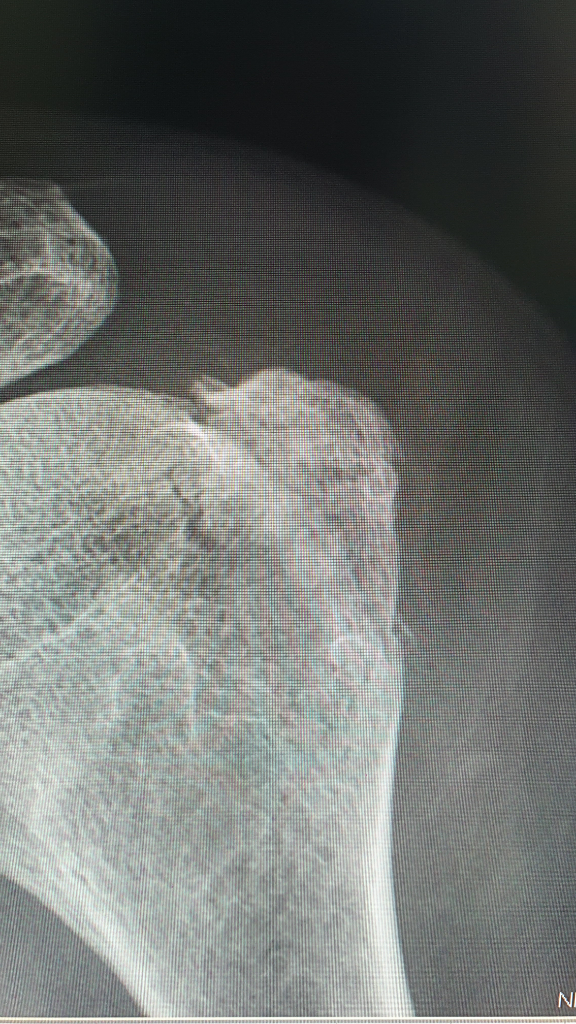

위는 오른쪽 어깨 사진입니다. (정상)

아래 사진이 문제의 왼쪽 어깨 사진입니다. (정상)

길가다가 넘어져서 어깨 골절 진단을 받았는데, 병원마다 수술 권하는 곳과 약물치료 우선 해보자는 곳으로 나뉘어져

회전근개가 부착되는 대결절부위의 골절로 위로 딸려 올라가고 있습니다

이럴 경우 적절하게 교정이 되지 않으면 향후 견봉과 계속 충돌을 하면서 통증 및 회전근개의

파열을 유발할 수 있어서 비수술적인 치료법의 성적이 좋지 않은 편입니다

어깨 전문병원의 의견을 고려하시기 바랍니다